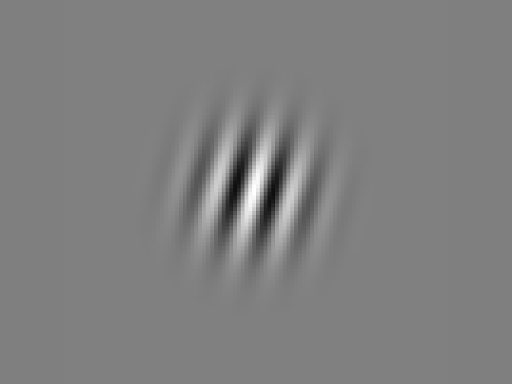

Gabor Patch Training

Visual stimuli for perceptual learning

Horizontal Pattern

Vertical Pattern

Based on brain plasticity principles to improve visual processing at the neural level

AI-powered adaptive training with Gabor patches that adjust to your visual threshold in real-time

Single Image Task

Detect and identify single Gabor patches at varying contrast levels

Distinguish between three similar images with subtle differences

Identify the darker image among multiple low-contrast stimuli

Detect spatial shifts in Gabor patch positions